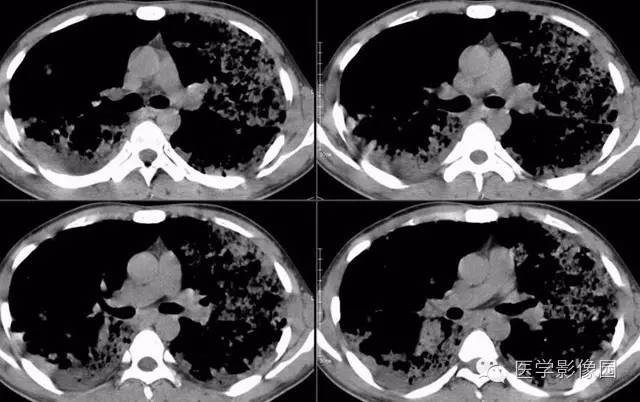

弥漫性肺泡细胞癌1例CT影像表现

病理结果:弥漫性肺泡细胞癌

弥漫性肺泡癌的主要临床及CT表现:临床表现无明显特征, 随着病情的进展, 咳嗽、 咳白痰、 进行性气促。CT表现 为病变分布有两种情况:病变累及一个肺段或肺叶;病变广泛分布于两肺。可归纳为5个特征性征象:蜂房征;支气管充气征;磨玻璃征;血管造影征;两肺弥漫分布的斑片状与结节影。